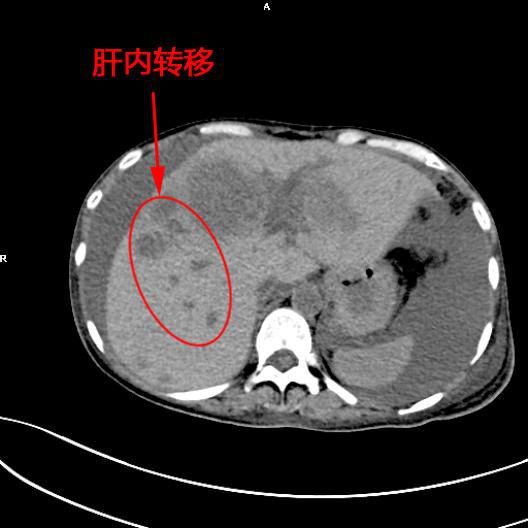

患者陳女士,57歲,汕頭潮南人,2個月前出現右上腹痛,在汕頭大型三甲醫院确診爲膽囊癌,因腫瘤爲晚期,已擴散至肝髒、十二指腸,患者放棄在汕頭治療,回家後自行采用中藥治療。近期右上腹痛加重,反複排黑便,遂來我院住院,診斷爲膽囊癌伴活動性出血。

5月11日下午,内三科主任李旭丹、影像科副主任胡志華上台施術。通過粵東領先的飛利浦DSA造影顯示,患者腫瘤供血血管豐富,膽囊動脈造影可見腫瘤染色明顯,有造影劑外溢,提示部分血管末梢有破裂出血現象,探查胃十二指腸動脈及腸系膜上動脈未見出血征像,豐富的血供使腫瘤能獲取大量的營養快速生長,血管末梢的破裂出血導緻患者反複黑便。

李旭丹主任在DSA引導下找到腫瘤的供血動脈——膽囊動脈,通過股動脈穿刺置入微導管将栓塞材料送達并釋放于腫瘤供血動脈,成功将動脈堵住,掐斷了腫瘤的供血。手術達到了預期目的,不但膽囊出血得到根除,也阻斷了腫瘤的營養供應,達到“餓”死腫瘤的目的,同時在腹腔幹灌注化療藥治療轉移病竈。